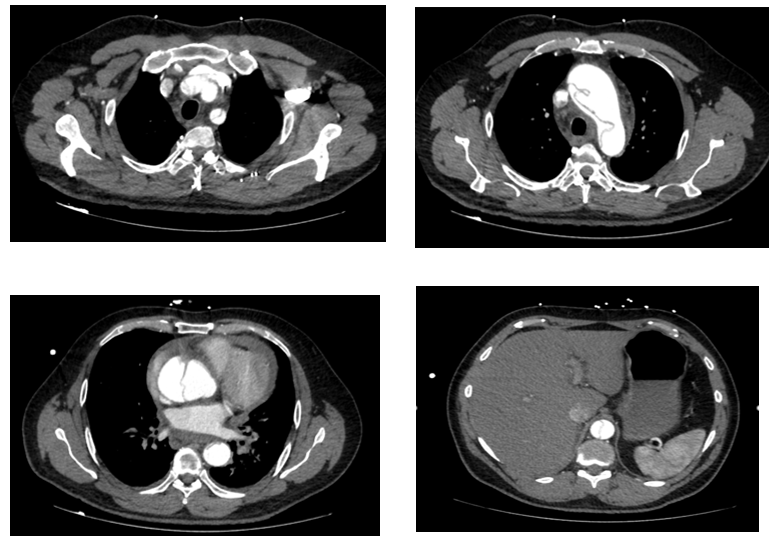

Fig 1

CT aortogram showed Stanford A thoraco-abdominal dissection with pre-existing abnormal ascending aorta. Unfortunately, shortly after returning from CT the patient deteriorated and suffered a cardiac arrest. Despite a prolonged resuscitation including an attempted pericardiocentesis, the patient did not survive.